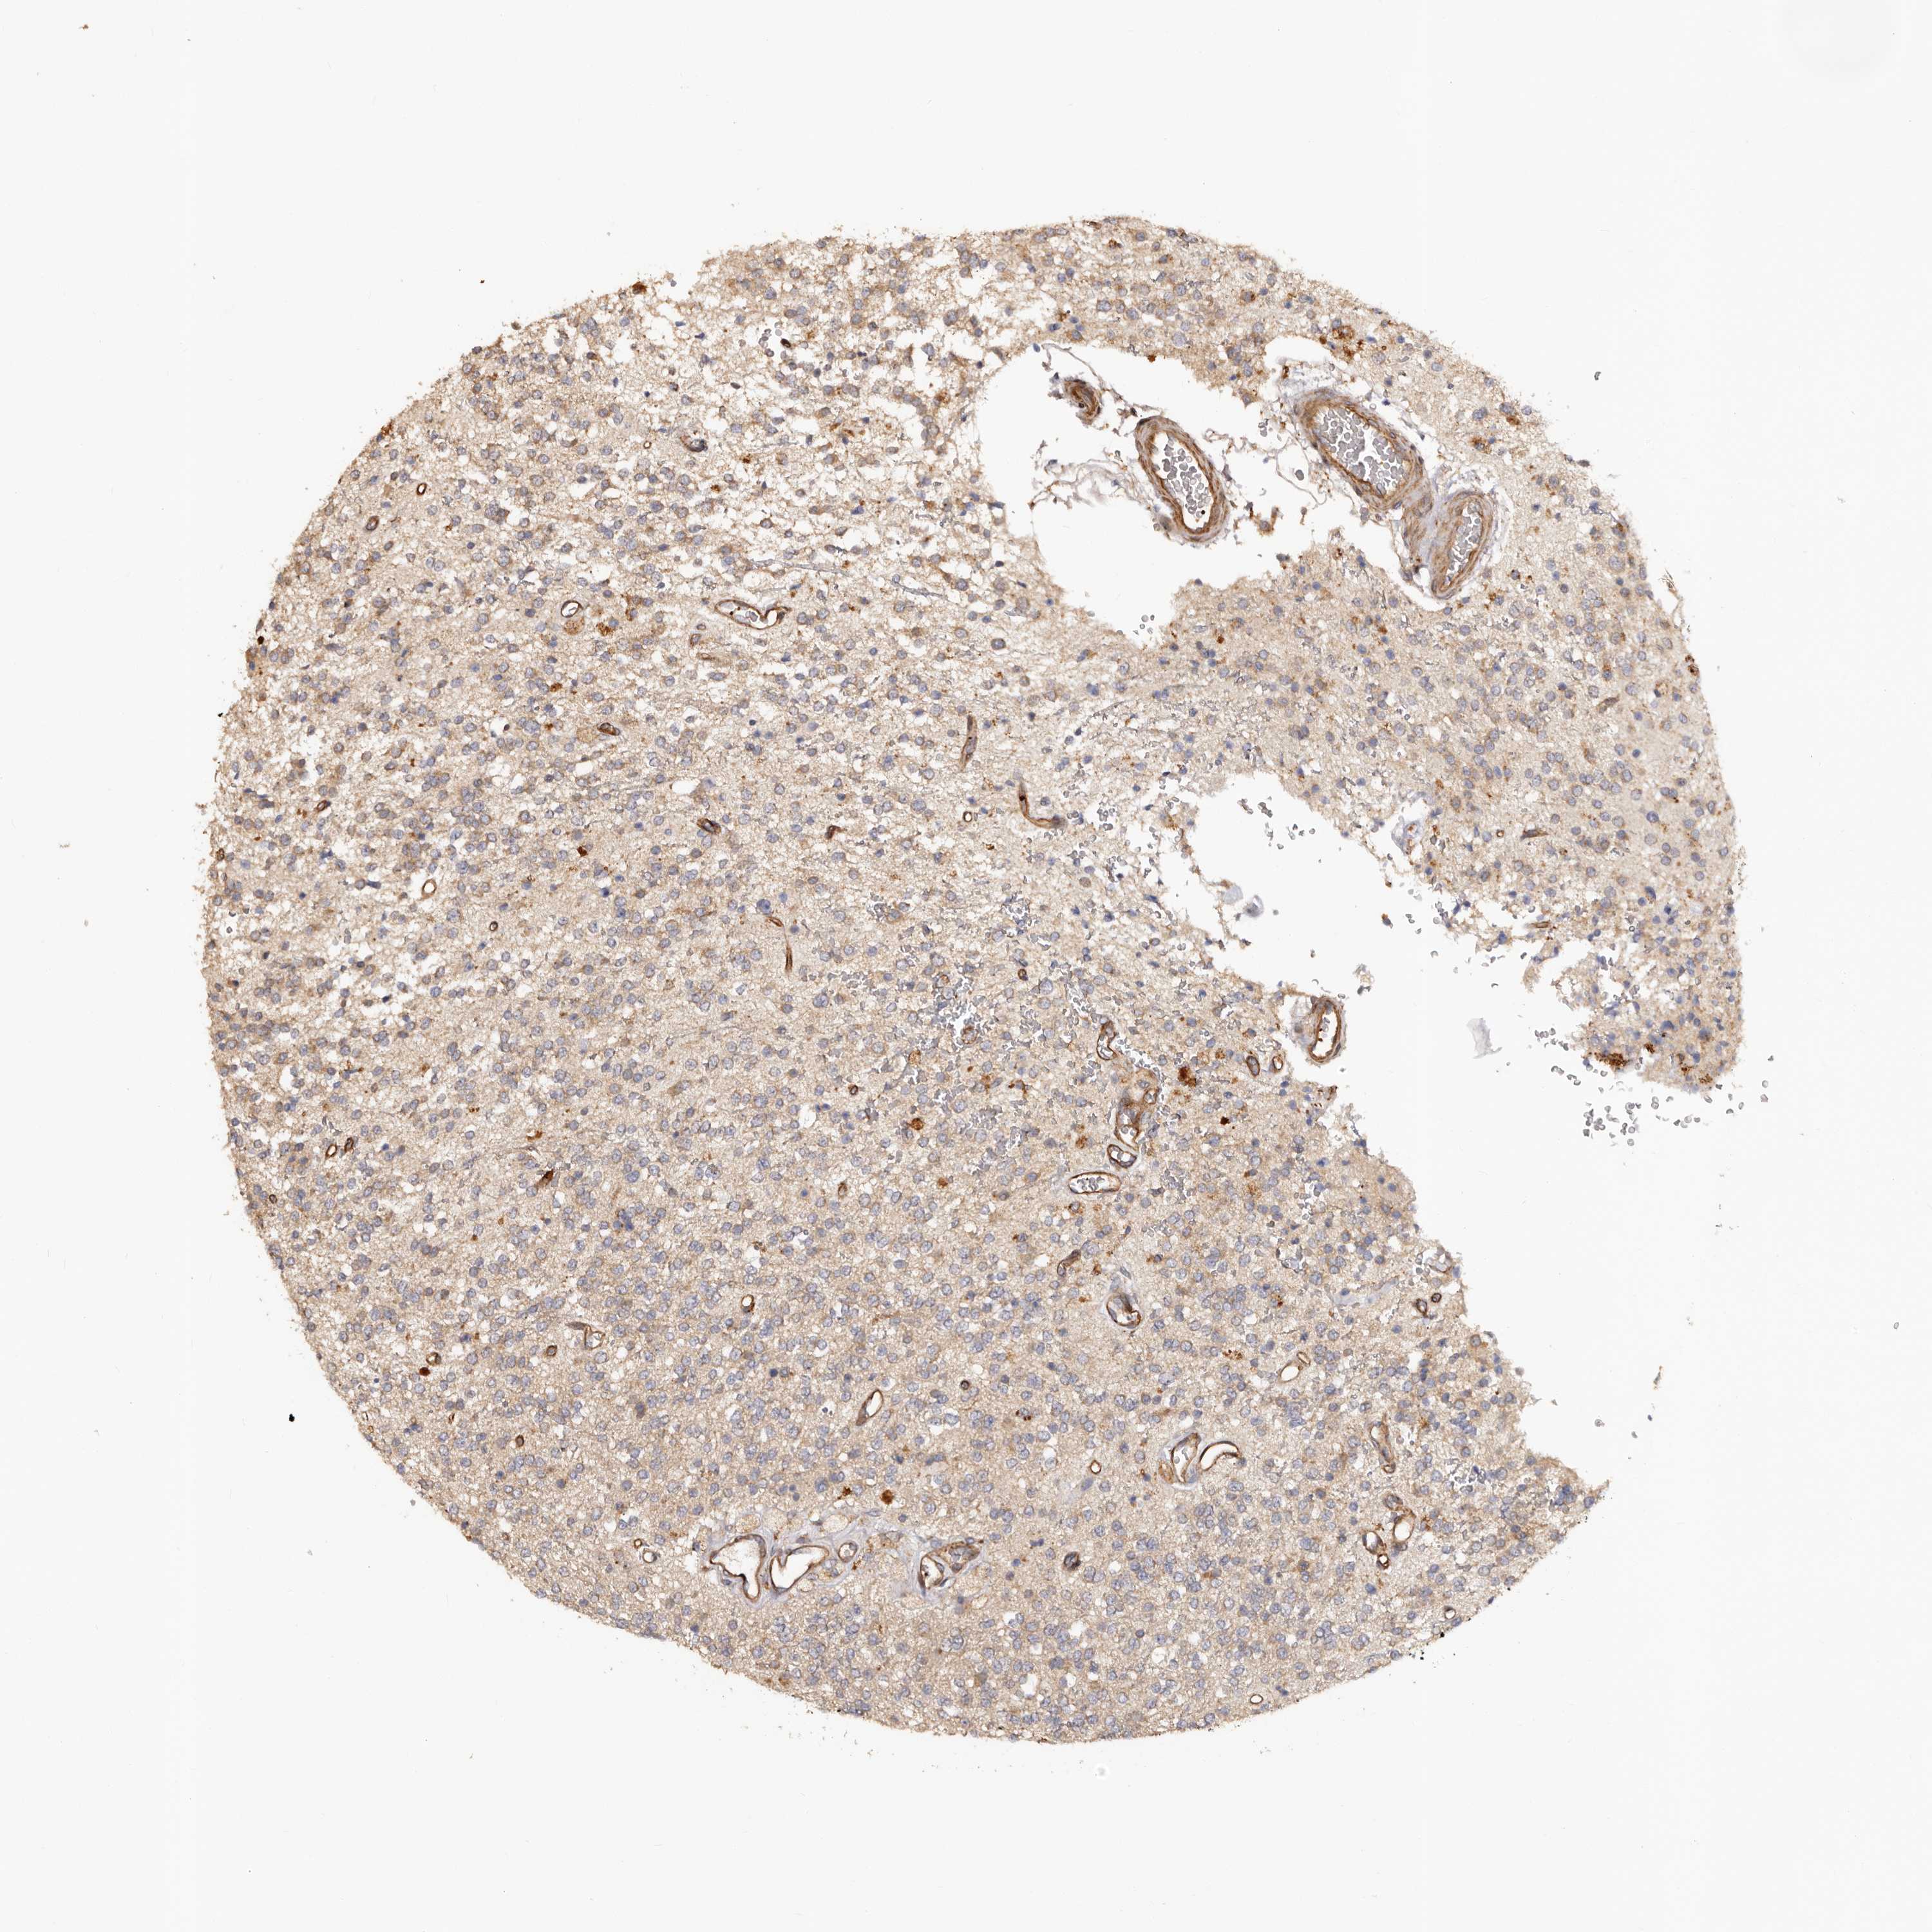

GLIOMA - Protein expressioni

A mouse-over function shows sample information and annotation data. Click on an image to view it in a full screen mode. Samples can be filtered based on level of antibody staining by selecting one or several of the following categories: high, medium, low and not detected. The assay and annotation is described here.

Note that samples used for immunohistochemistry by the Human Protein Atlas do not correspond to samples in the TCGA dataset.

Antibody stainingi

Antibody staining in the annotated cell types in the current human tissue is reported as not detected, low, medium, or high, based on conventional immunohistochemistry profiling in selected tissues. This score is based on the combination of the staining intensity and fraction of stained cells.

Each image is clickable and will lead to virtual microscopy that enables deeper exploration of all samples and also displays staining intensity scores, fraction scores and subcellular localization as well as patient and tissue information for each sample.

Antibody HPA003166

Antibody HPA064702

Staining

High

Medium

Low

Not detected

Intensity

Strong

Moderate

Weak

Negative

Quantity

>75%

75%-25%

<25%

None

Location

Nuclear

Cytoplasmic/membranous

Cytoplasmic/membranous,nuclear

Glioma, malignant, High grade

Glioblastoma, NOS

Glioma, malignant, NOS